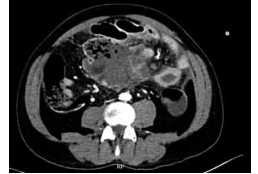

Homem de 53 anos, com quadro de linfoma difuso de

grandes células B com grande conglomerado linfonodal

no mesentério. Iniciou esquema quimioterápico (CHOP)

e, após 1 semana da primeira infusão, apresenta quadro de dor abdominal intensa, procurando o pronto-socorro. Apresenta-se com abdome distendido, doloroso à

palpação de mesogastro, ruídos hidroaéreos ausentes.

FC: 113 bpm e PA: 107 x 74 mmHg. Exames relevantes: hemoglobina: 12 g/dL; hematócrito: 36%; leucócitos:

18.500/mm3

; neutrófilos segmentados: 85%; bastonetes:

10%; plaquetas: 420.000/mm3

; PCR: 220 mg/L. Realizou

ainda a tomografia de abdome demonstrada a seguir:

Durante a abordagem, no intraoperatório, encontra-se extensa infiltração mesentérica.

Dessa forma, qual conduta deve ser priorizada?